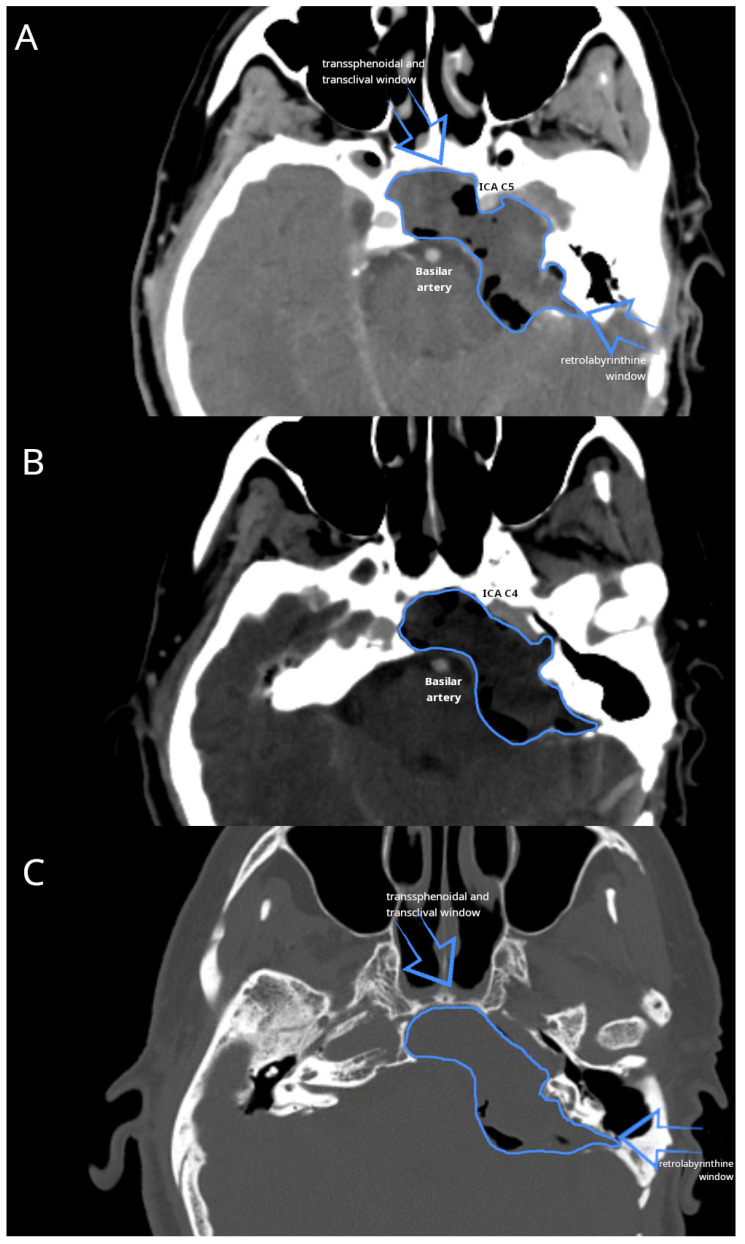

Background and Clinical Significance: Petrous bone cholesteatoma is a rare and complex condition that poses significant challenges in terms of its diagnosis and treatment. This benign yet locally aggressive lesion can cause extensive destruction of the surrounding structures, potentially leading to serious complications. Case Presentation: We present a case of extensive petrous bone cholesteatoma involving nearly the entire skull base. High-resolution CT and MRI were used to assess the extent of the lesion and its relationship with critical neurovascular structures. The cholesteatoma extended from the petrous apex to the clivus, involving the internal auditory canal and Meckel's cave, encasing the internal carotid artery, and compressing the brainstem. The surgical strategy included combined endoscopic transsphenoidal and transclival techniques with a retrolabyrinthine approach. The endoscopic component provided access to the anterior and central skull base regions, whereas the retrolabyrinthine approach allowed us to gain access to the posterior petrous area. Careful dissection was performed to separate the cholesteatoma from the internal carotid artery and the brainstem. Neuromonitoring was performed throughout the procedure to ensure cranial nerve integrity. This combined approach enabled gross total resection, and postoperative imaging confirmed successful tumor removal. The patient's recovery was uneventful, and no new neurological deficits were observed. Conclusions: The successful management of this complex case demonstrates the efficacy and safety of combining endoscopic surgical approaches for extensive skull base cholesteatomas. This multi-corridor approach allows for maximal tumor resection while also minimizing the risks to critical neurovascular structures.